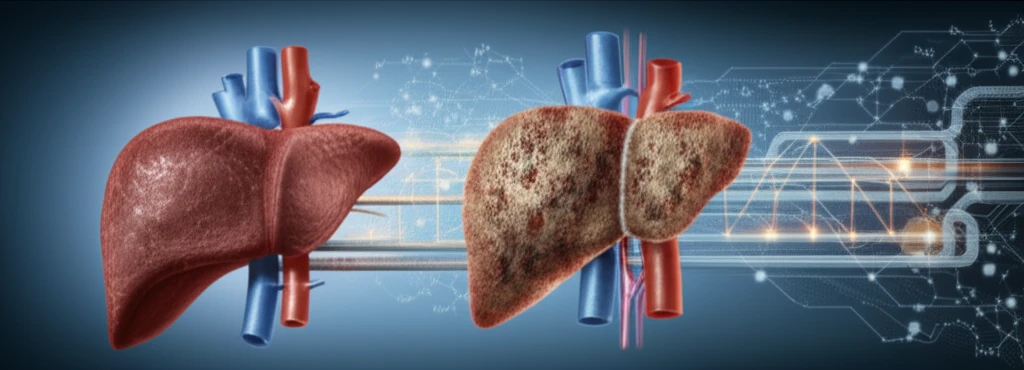

Obesity rates are climbing, and with them, a surge in metabolic disorders across the Western world. One of the most concerning is non-alcoholic fatty liver disease (NAFLD), a condition where the liver accumulates excess fat, mirroring the body’s struggle to process increasing caloric intake. NAFLD isn't just a benign condition; it's a gateway to more severe health problems, including liver cancer.

The liver is the body's metabolic command center, responsible for processing proteins, lipids, and carbohydrates. It acts as both a storage facility and a distribution hub, absorbing, converting, and releasing essential substances. When this carefully orchestrated system malfunctions, the consequences can be dire, ranging from simple steatosis (fatty liver) to the more aggressive hepatocellular carcinoma (HCC).

The GH-JAK2-STAT5 pathway is central to understanding and treating fatty liver disease and preventing liver cancer. Impairing this pathway through the deletion of Stat5 or Jak2 leads to significant changes in lipid metabolism and accumulation of lipids. While both STAT5 and JAK2 are crucial for liver homeostasis, they play different roles in liver cancer development, partly due to differences in ROS generation and clearance. Targeting JAK2 may reduce oxidative stress and prevent liver damage.